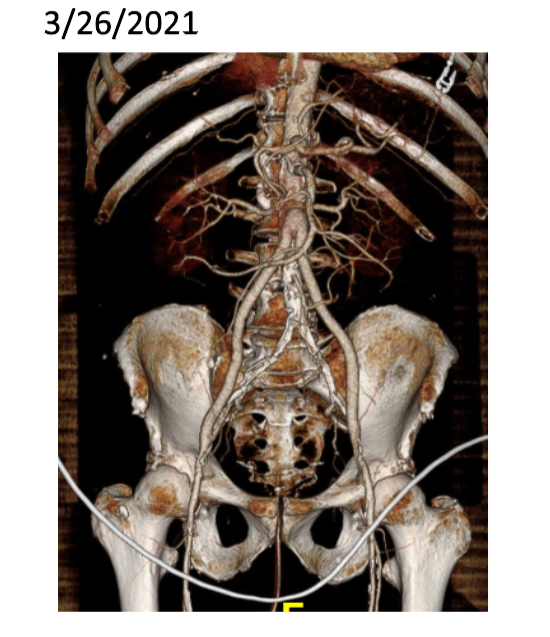

The patient was a 50 something year old man who I took care of in 2016 before I left for Abu Dhabi. He had a background of hypertension, hypercholesterolemia, and IDDM with chronic immunosuppression for rheumatoid arthritis. For several weeks he had rest pain in his feet and impending gangrene of his left great toe. More worrisome was the development of punched out ulcers on his groin crease resulting in weeping wounds after a bout of cellulitis. He had no palpable femoral pulses. Pulse volume recordings showed flat lines from the thigh to the feet.

CTA of the abdomen and pelvis with runoff showed aortic occlusion due to heavily calcified plaque with reconstitution of the external iliac arteries via the internal iliac arteries. The common femoral arteries were only mildly diseased and there was patent runoff.

Centerline up right femoral into aorta shows occluded aorto-iliac segment and diseased external iliac artery.

Centerline up left femoral into aorta shows mirror image of disease on left side

In the five years since the operation, he has needed an SMA stent and has devloped worsening CKD and autoimmune diseases. But one of the gratifying things is he healed his wounds on this groins and thighs and the left hallux, and pain has never recurred. He had a contrast CT at the 5 year point (figure) showing a widely patent graft, and he sought me out when he heard that I was back in Cleveland.